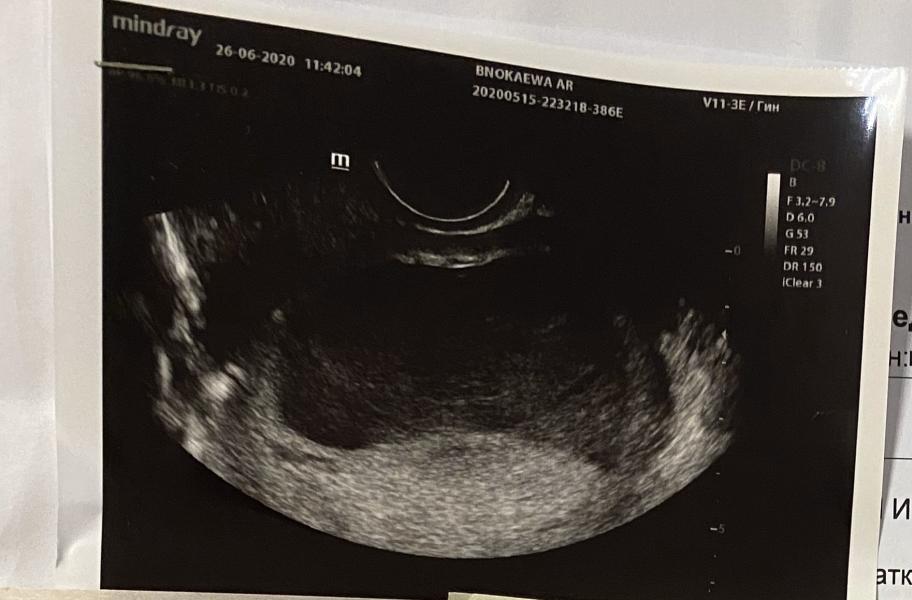

Узи показывает гематому в !4 раза больше, но как я понимаю, в другом месте. С противоположной от хориона как объяснила врач! 80х28мм и не менее 100мл крови внутри😭

Диагноз: заоболочечная гематома больших размеров.